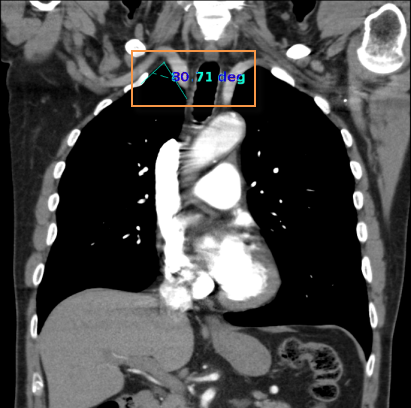

To obtain an angle measurement:

![]() - Measure Angle

- Measure Angle